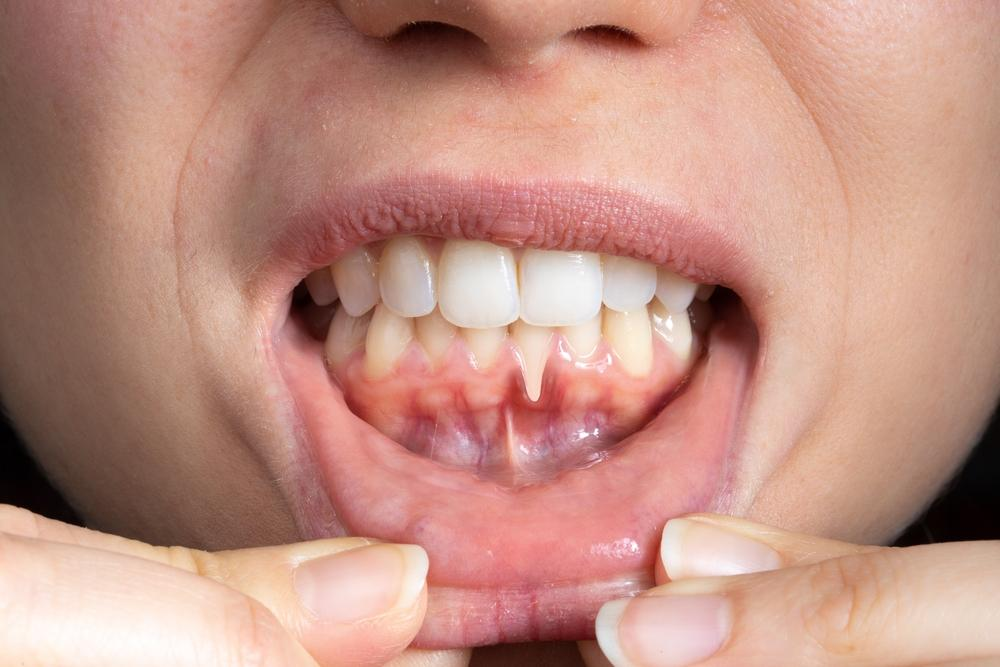

Gum health is the foundation of a strong, confident smile. However, issues like bleeding gums, swelling, and bad breath are often signs of gingivitis, the earliest stage of gum disease. If left untreated, it can progress to periodontitis, a severe infection that damages the bone supporting your teeth.

Gingivitis – Gingivitis is the first stage of gum disease. It occurs when plaque buildup causes inflammation, redness, and bleeding gums. The damage is reversible at this stage with proper care and professional cleaning, especially for patients seeking expert dental care in dlf phase 4.